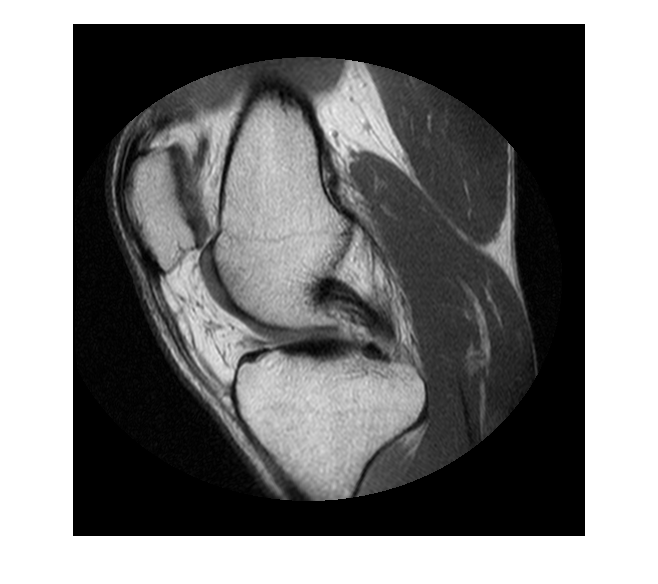

Считайте данные MRI в рабочую область.

im = dicomread('knee1.dcm');

Сегментируйте изображение MRI и выберите две самых больших области маски.

segmentedLabels = imsegkmeans(im,3); boneMask = segmentedLabels==2; boneMask = bwareafilt(boneMask, 1);

Получите координаты контуров двух сегментированных областей.

blocations = bwboundaries(boneMask,'noholes');

Преобразуйте местоположения, возвращенные bwboundaries к x, y порядок.

pos = blocations{1};

pos = fliplr(pos);

Отобразите изображение.

figure hImage = imshow(im,[]);